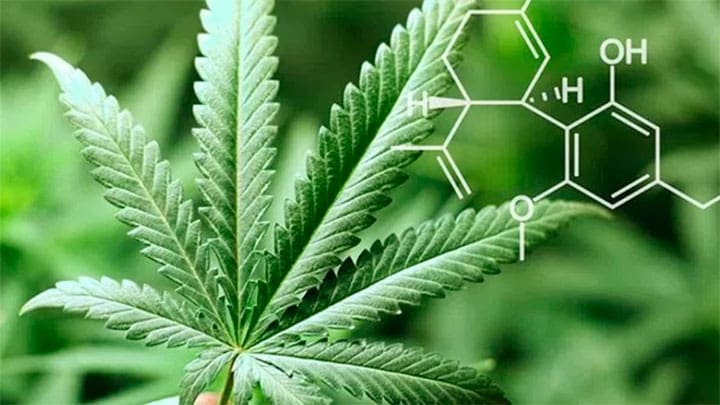

México.- La Comisión Federal para la Protección contra Riesgos Sanitarios (Cofepris), consideró que para 2018 las farmacias mexicanas ya tendrán a la venta medicamentos derivados de...